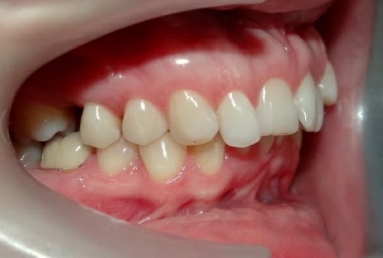

SAPPHIRE ORTHODONTIC DEVICE